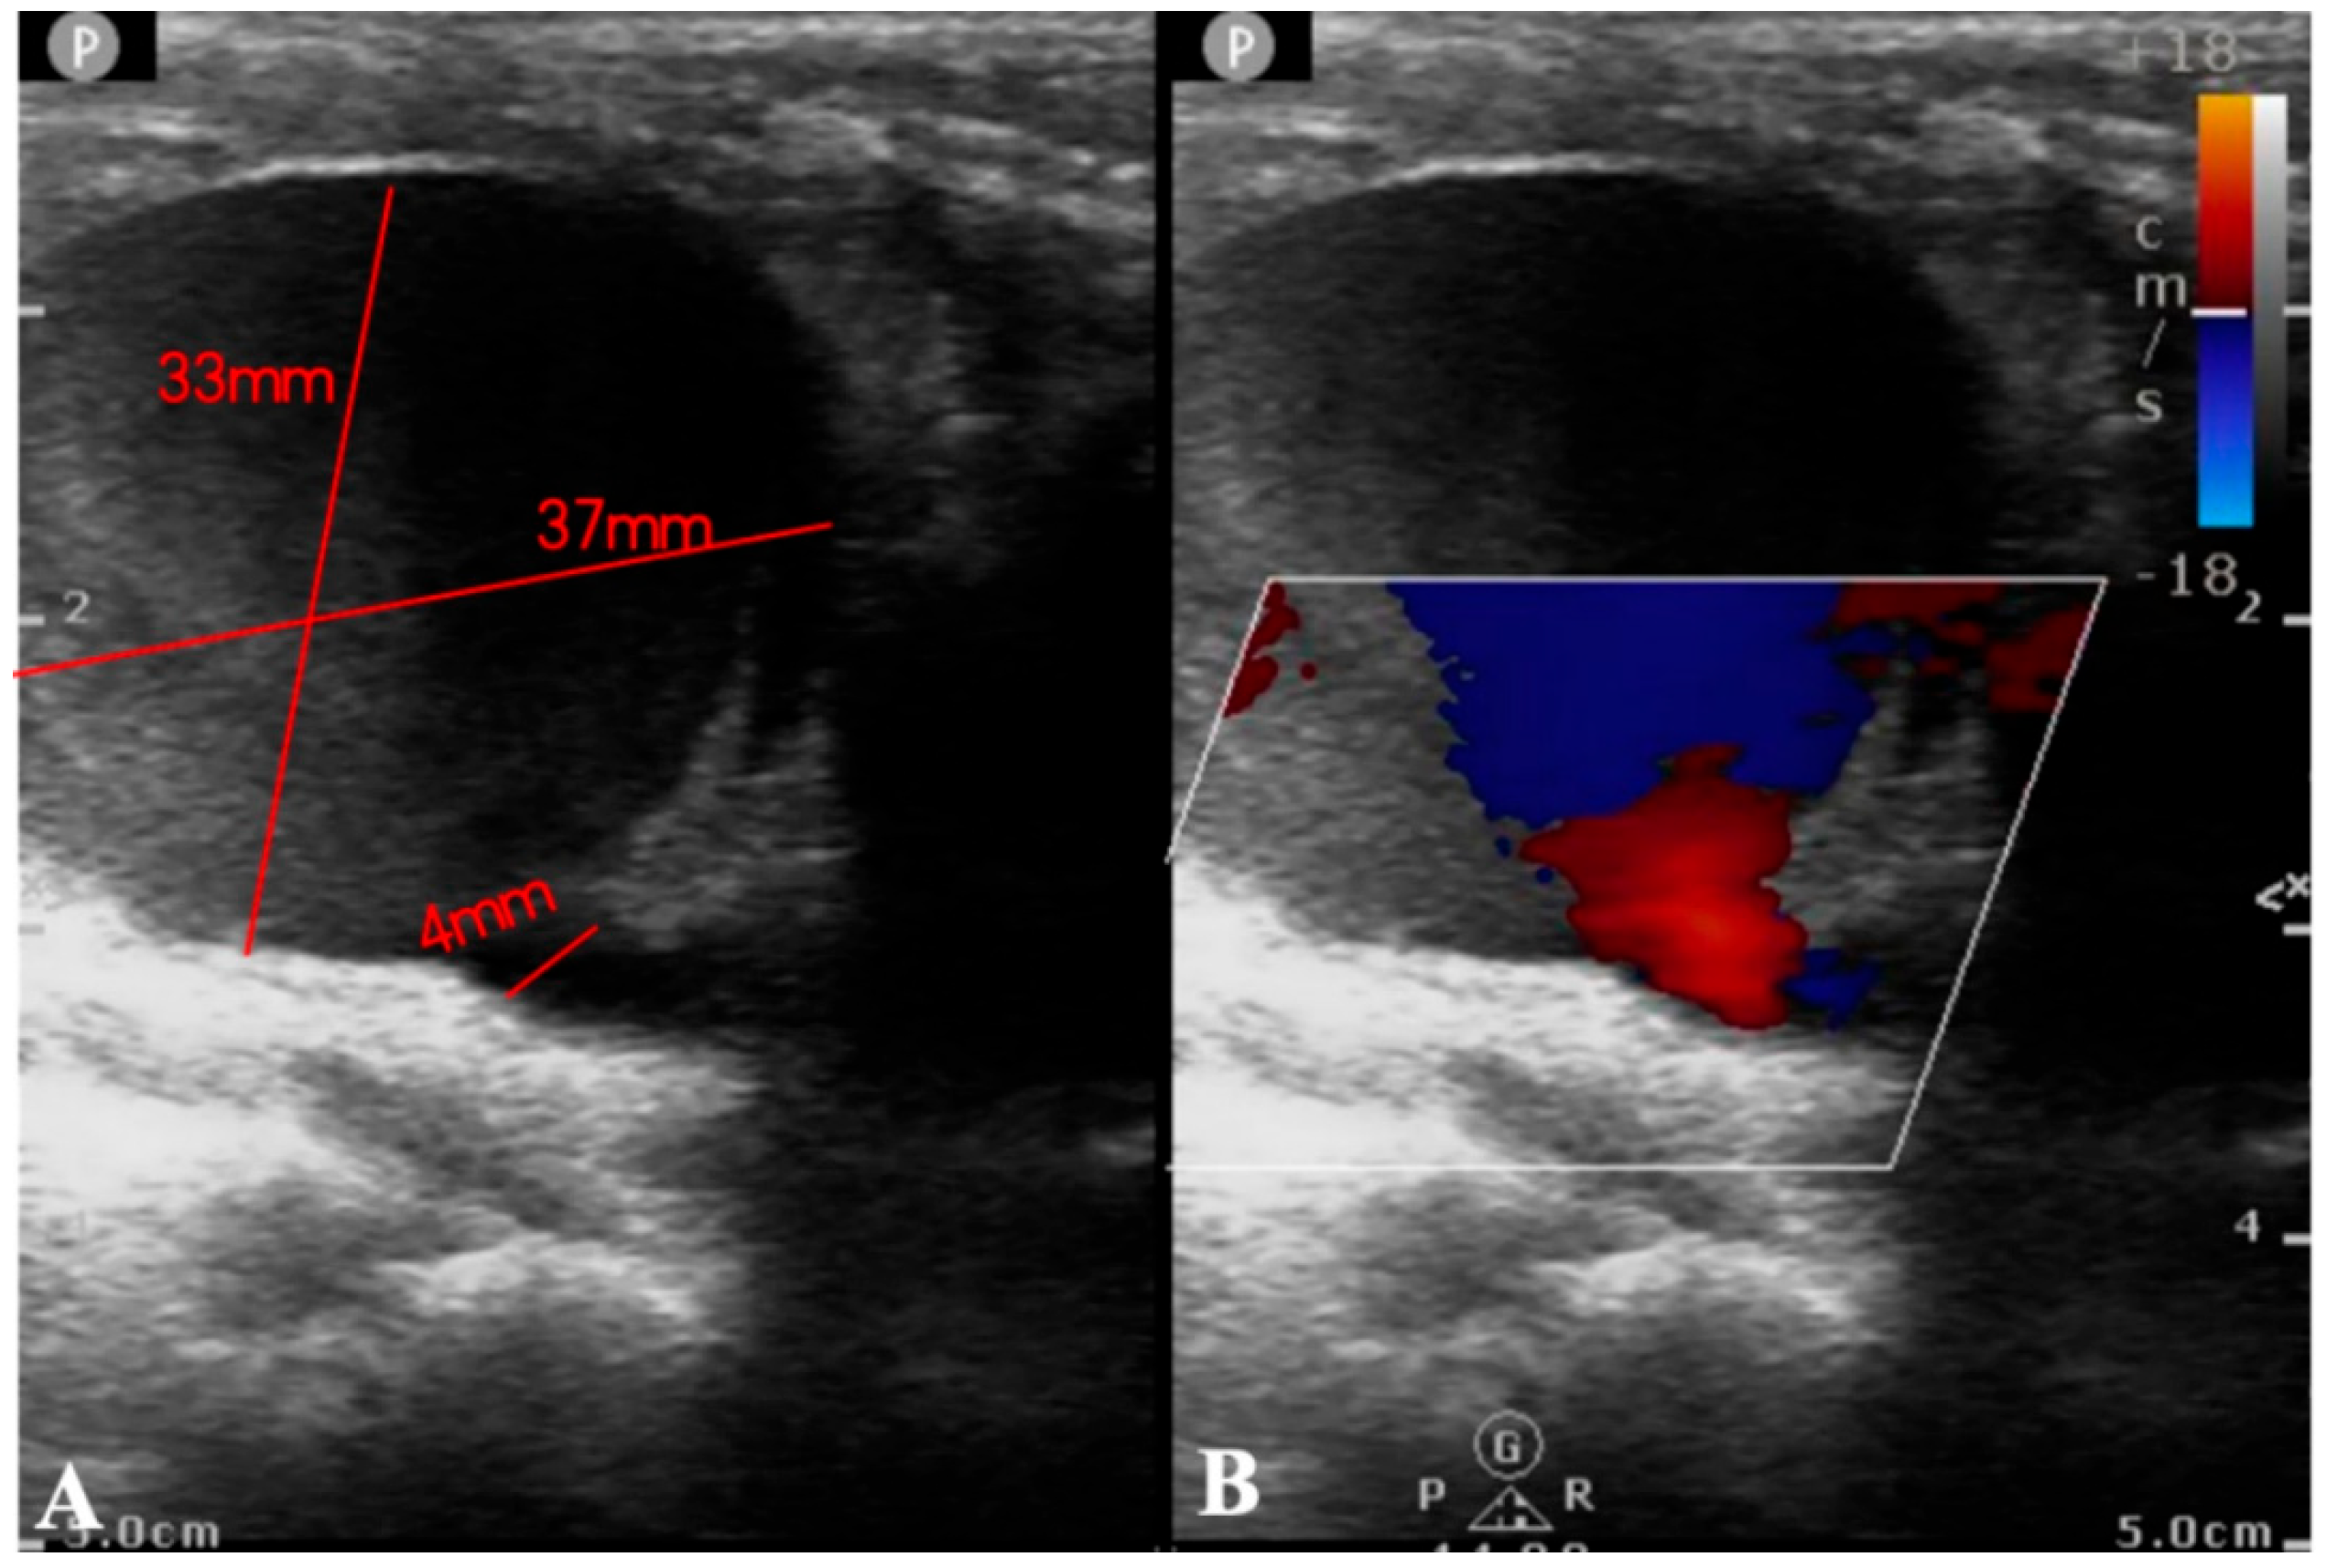

Figure 2: Ultrasound examination reports. (A): Ultrasound examination revealed a low echogenicity area of approximately 37 × 33 mm2, contiguous with the internal carotid artery, featuring an orificium fistulae with a diameter of 4 mm. (B): Color Doppler Flow Imaging (CDFI) demonstrated a color flow jet entering from the internal carotid artery, with visible red and blue turbulent flow signals within.